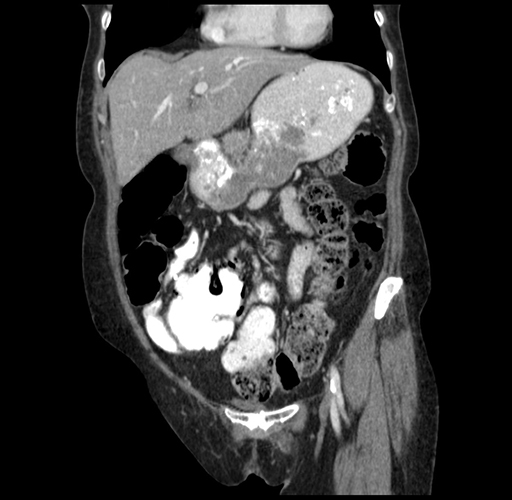

Pre-Chemo: Coronal Venous

Coronal Venous